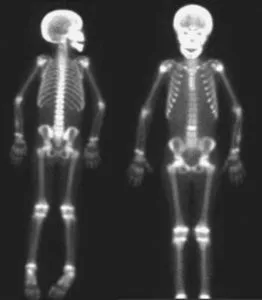

Tale patologia delle ossa colpisce soprattutto le persone sopra i cinquant’anni. La malattia si presenta con un disequilibrio nell’eliminazione e nel rinnovamento delle cellule ossee e porta ad una deformazione delle stesse dovuta ad un’ipertrofia in lunghezza e larghezza di quelle colpite.

Può riguardare sia le ossa degli arti inferiori sia quelle del cranio che vanno espandendosi rispetto a quelle del viso, facendole apparire quindi più piccole e dando loro un aspetto simile al volto di una scimmia. A queste deformazioni si aggiungono disturbi vasomotori e cardiovascolari.